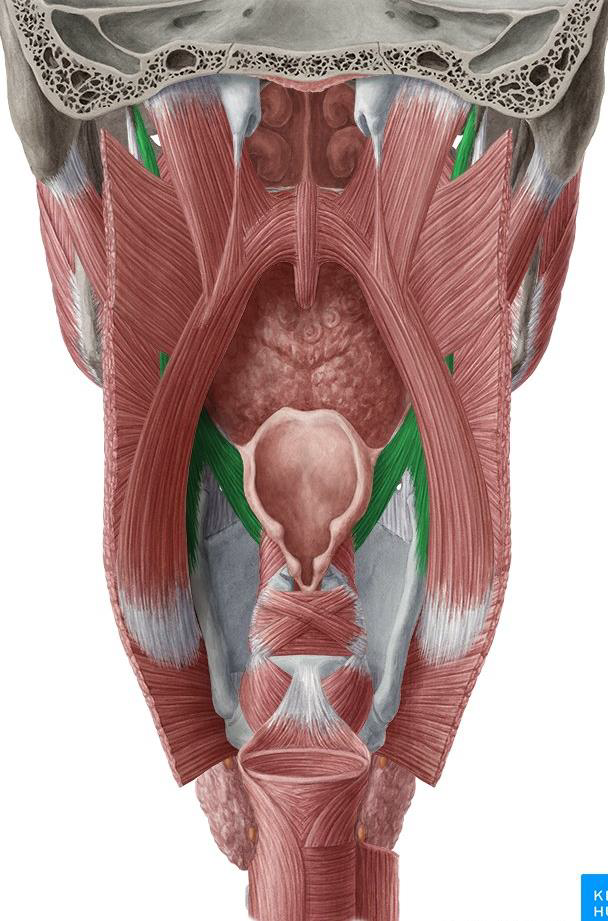

內部

Vagus 支配

- Palatoglossus m

- palatoglossal fold 下

- Palatine aponeurosis lateral side of tongue

- Palatopharyngeus m

- palatopharyngeus fold下

- Hard palate and palatine aponeurosis Thyroid cartilage and pharyngeal wall

- salpingopharyngeus m.會合

- Salpingopharyngeus m.

- salpingopharyngeal fold下

- Cartilage of pharyngotympanic tube(耳咽管軟骨) thyroid cartilage and pharyngeal wall

- Levator veli palatine m.

- From Scaphoid fossa

V3支配

- Tensor veli palatini m.

- 增加軟顎強度

- 打開耳咽管

- 繞過 pterygoid process